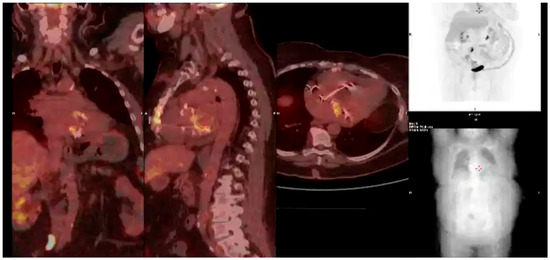

Multimodality Imaging in Infective Endocarditis: A Clinical Approach to Diagnosis

by Leonardo Brugiatelli, Francesca Patani, Carla Lofiego, Martina Benedetti, Irene Capodaglio, Pongetti Giulia, Francioni Matteo, Paolini Enrico, Nazziconi Marco, Kevin Maurizi, Furlani Giulia, Massari Arianna, Luciani Simone, Anselmi Benedetta, Gatti Chiara, Schicchi Nicolò, Fogante Marco, Tarsi Giovanni, Dello Russo Antonio, Di Eusanio Marco, Marini Marco and Fabio Vagnarelliadd Show full author list remove Hide full author list

Medicina 2025, 61(12), 2241; https://doi.org/10.3390/medicina61122241 - 18 Dec 2025

Infective endocarditis (IE) is a life-threatening condition with a rising incidence, demanding rapid and precise diagnosis. While echocardiography remains the cornerstone of initial evaluation, its limitations in complex cases—such as those involving prosthetic valves or cardiac devices—are well-known. This review synthesizes current evidence [...] Read more.

Infective endocarditis (IE) is a life-threatening condition with a rising incidence, demanding rapid and precise diagnosis. While echocardiography remains the cornerstone of initial evaluation, its limitations in complex cases—such as those involving prosthetic valves or cardiac devices—are well-known. This review synthesizes current evidence and guidelines to outline a practical, multimodality imaging approach for IE. We emphasize that integrating advanced techniques like cardiac computed tomography (CT) and [18F]-fluorodeoxyglucose positron emission tomography/computed tomography (FDG PET/CT) early in the diagnostic pathway, particularly in high-risk scenarios, significantly enhances diagnostic certainty, guides therapeutic decisions, and improves patient outcomes. A tailored imaging strategy, driven by clinical presentation and integrated within a multidisciplinary endocarditis team, is paramount for modern IE management. Full article

(This article belongs to the Special Issue Diagnosis and Treatment of Valvular Heart Diseases)

Show Figures

Figure 1